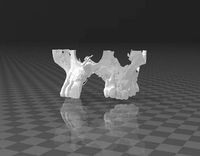

cg_trader

free

maxilla

...maxilla

cg trader

maxilla 3d scan maxilla dental skull bone tooth medicine dentist science character anatomy

cg_trader

free

maxilla

...maxilla

cg trader

3d maxilla real .

3d scan mandibilar maxilla mandibular bone skull tooth character anatomy